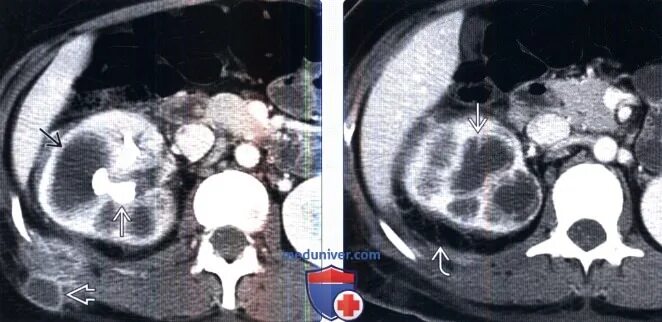

Пиелонефрит кт